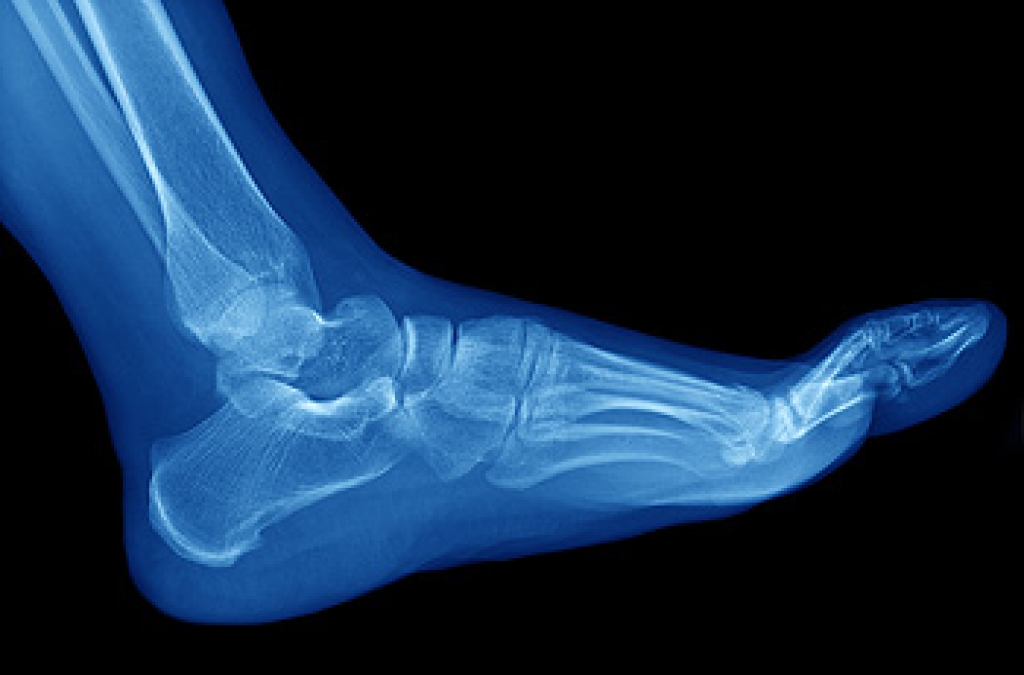

The bones that are located in the feet can be affected by stress fractures. Stress fractures are hairline fractures that can gradually develop from overuse. They can form as a result of a sudden change in footwear, running on uneven surfaces, or suddenly increasing the intensity in running and jumping activities. Common symptoms that many patients experience can include tenderness surrounding the injured area, in addition to severe pain when the activity is completed. Mild relief can be found when the affected foot is elevated, and this may help to increase circulation to the heart. If you feel you have endured a stress fracture in your foot, it is advised that you seek the counsel of a podiatrist who can properly diagnose and treat stress fractures.

Stress fractures occur in the foot and ankle when muscles in these areas weaken from too much or too little use. The feet and ankles then lose support when walking or running from the impact of the ground. Since there is no protection, the bones receive the full impact of each step. Stress on the feet can cause cracks to form in the bones, thus creating stress fractures.

Pain from the fractures occur in the area of the fractures and can be constant or intermittent. It will often cause sharp or dull pain with swelling and tenderness. Engaging in any kind of activity which involves high impact will aggravate pain.